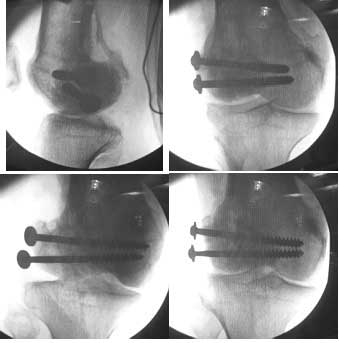

This was fixed temporarily, bone grafted with tricortical struts, and fixed by two cancellous screws. The fragment was not large enough to afford any fixation to a plate or such implant, and the screws held it compressed well to the rest of the distal femur.

Post-op - limb is well aligned, rom 0-30, but I am not pushing that right now, for the next two or three weeks.

Further plan - hope that the screws hold the fragment appropriately till union, but if the stability on table is anything to judge by, that should not be a problem.

Pictures attached.